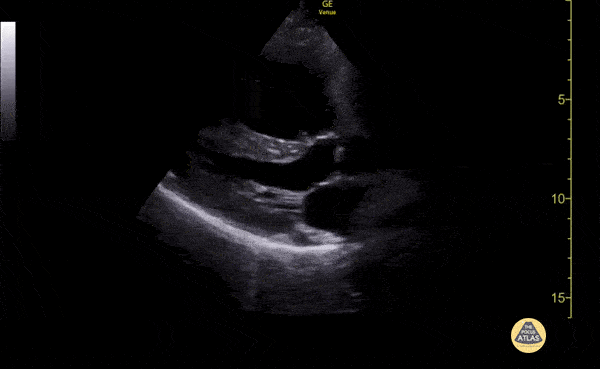

This clip demonstrates severe right ventricular enlargement seen on a parasternal long axis view. The patient had developed cor pulmonale from longstanding COPD. Pooja Belligund